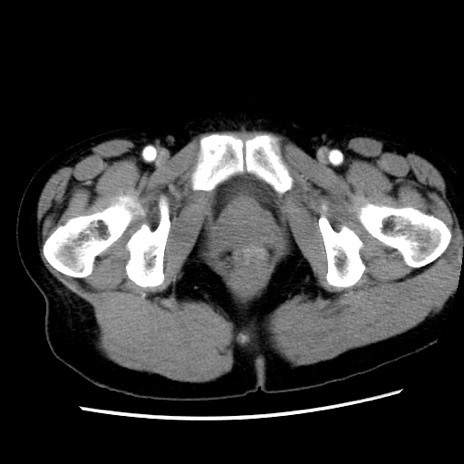

矢状断像

【症例】 50歳代女性

【主訴】 腹痛

【現病歴】前日生レバーを食べた。今朝に排便あり。 昼前に突然発症の腹痛を生じ、当院救急外来を受診した。

【既往歴】 子宮筋腫にてで子宮全摘後

【身体所見】 意識清明、腹部:平坦、軟、下腹部やや左を中心に圧痛・反跳痛あり、筋性防御あり

【データ】WBC 7800、CRP 0.07